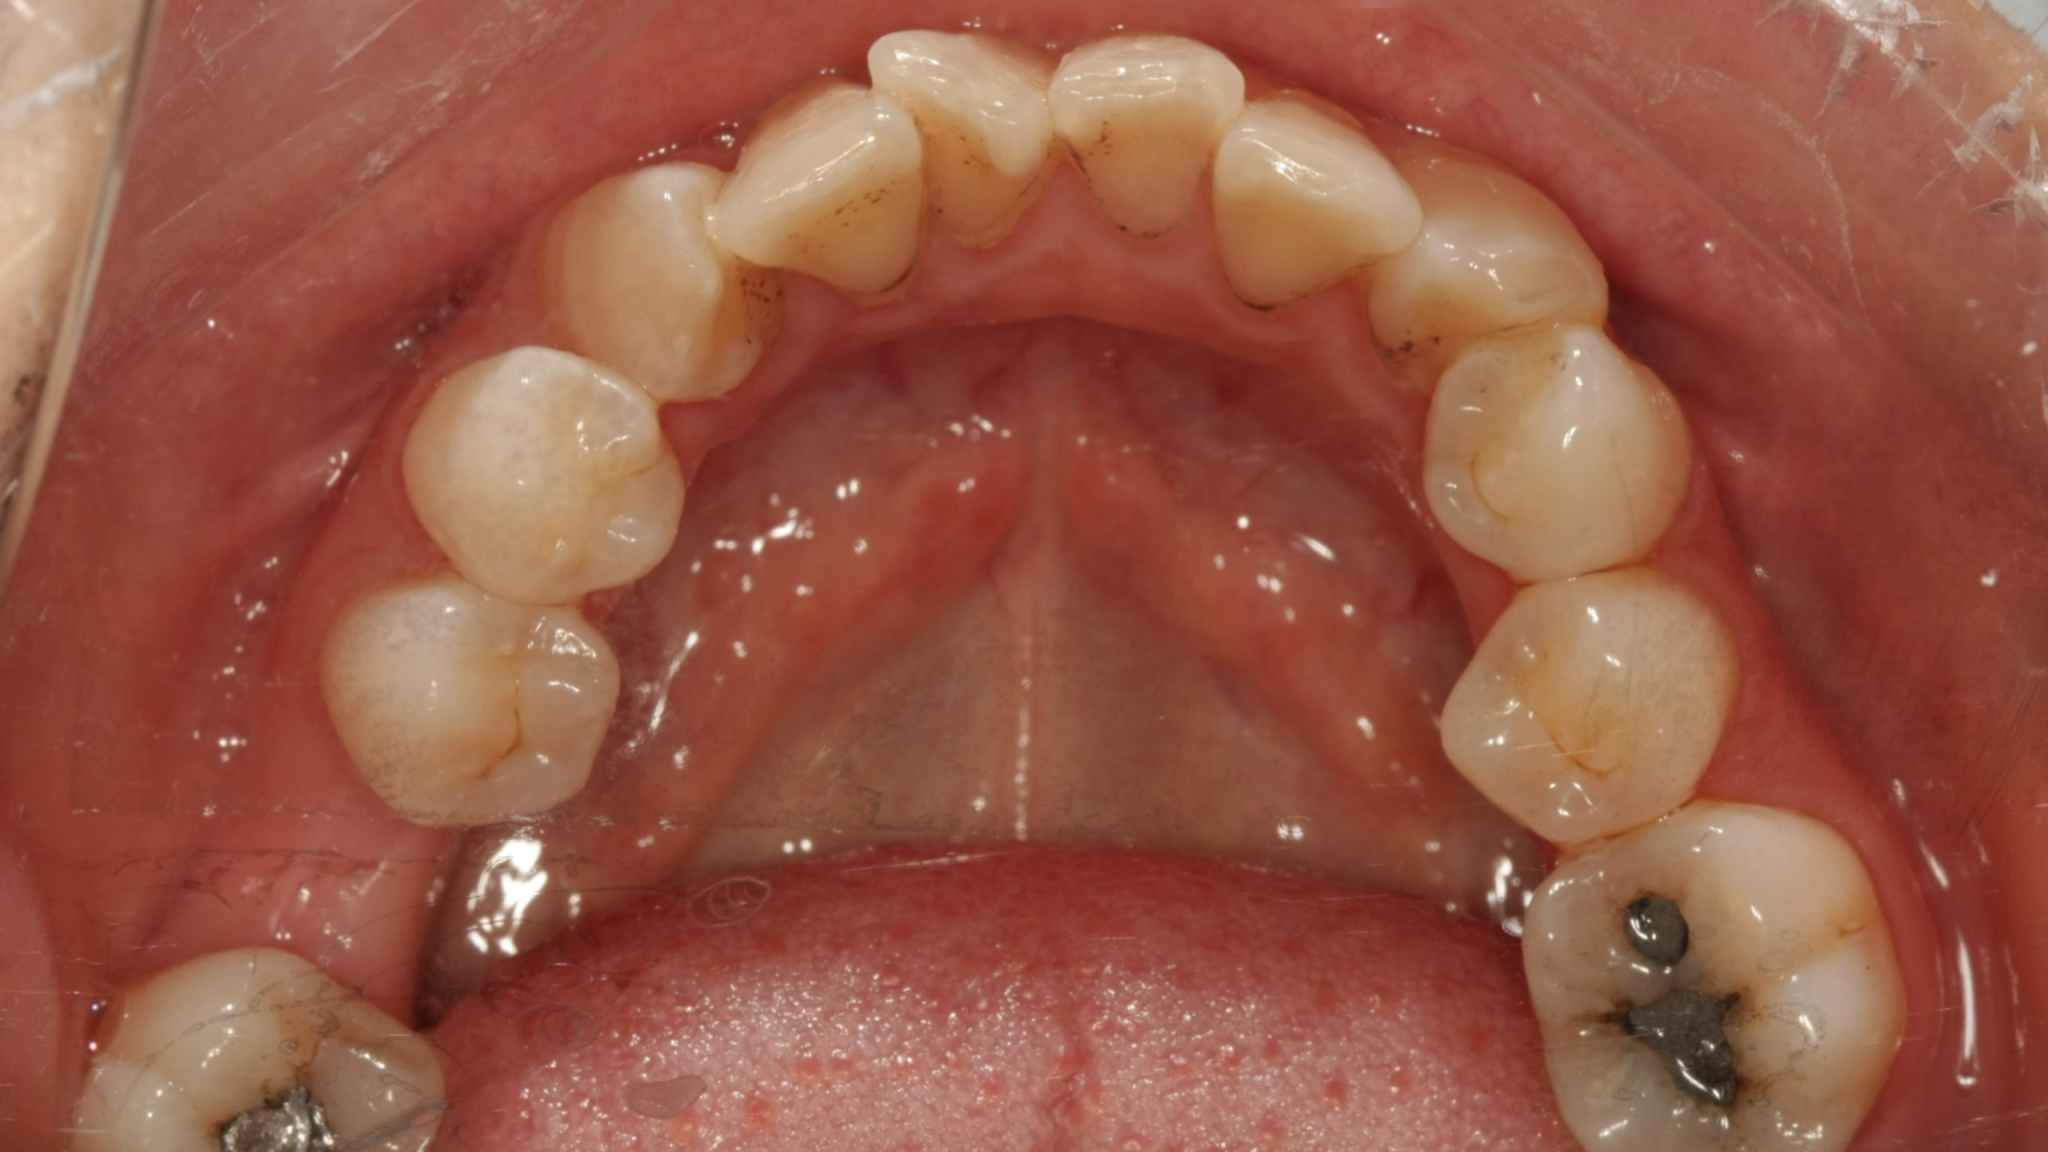

Preoperative photo

Physical exam: 46 missing, the alveolar was blade-shaped, the mucosal color was normal, and the width of the keratinized gingiva on the cheek and lingual crest was about 2mm. The gap in the missing area is normal, 47 is mesial-inclined, loose (-), the antagonist is normal, and the occlusal gap is normal.